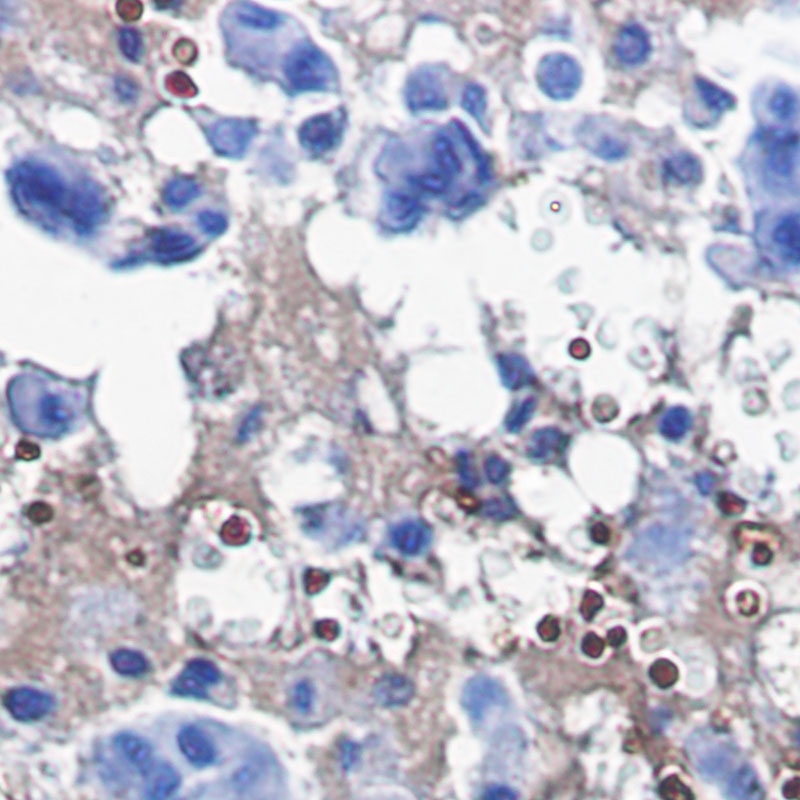

Immunohistochemistry of Catalase in paraffin-embedded Human breast cancer tissue using Catalase Rabbit mAb at dilution 1/1.